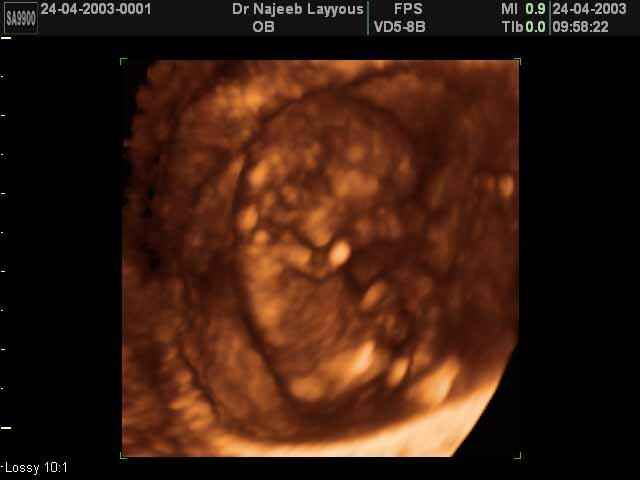

3D First Trimester Ultrasound Scan Photos ( Early Pregnancy Ultrasound Photos ) | Dr N Layyous